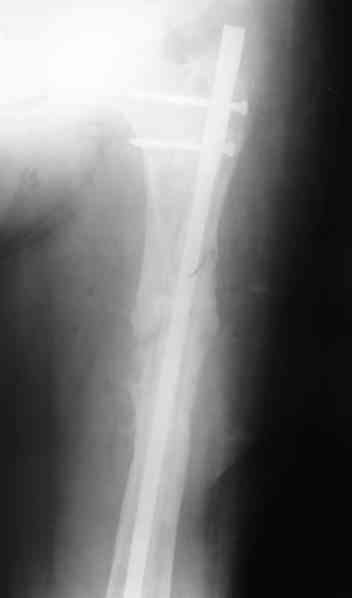

1, 2, 3, 4 - рентгенограммы бедра от 8 августа этого года (через четыре месяца после операции);

4, 5, 6 - рентгенограммы бедра и фотографии пациентки (прошу прощения за низкое качество рентгеновских снимков) от 7 сентября 2007 г.